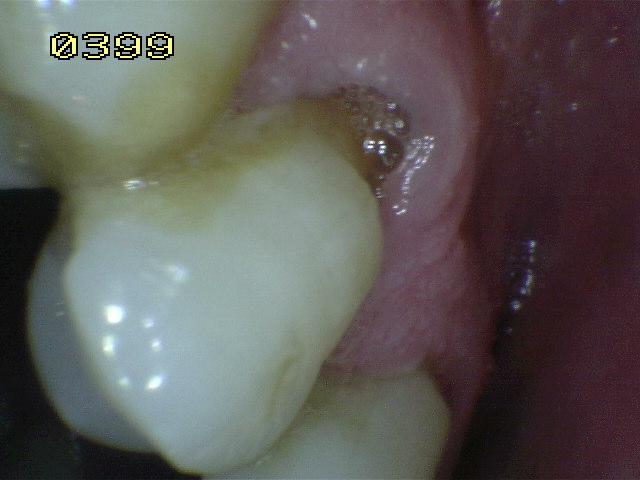

Sonda

Código 2: Hay una zona claramente delimitada en la superficie de la raíz o en la unión cemento-esmalte (UCE) que es una cavidad de color (claro, oscuro, marrón  y negro) y  hay presencia de  pérdida del contorno anatómico mayor a 0,5 mm. (cavidad presente) detectable también con sonda periodontal.

• Cuando la superficie de la corona y la raíz estén afectada por caries deben ser identificadas  independientemente.  En caso de duda porque la lesión de caries se encuentra en la unión cemento-esmalte (UCE)  debe analizarse que superficie esta más afectada o que se  extienda por lo menos 1 mm o más allá del limite de la unión cemento esmalte (UCE), en ambas direcciones cervico-incisal y cervical apical, debe considerase cual es la más extensa aplicando la regla del  50% , si existe igualdad el examinador debe decidir si la lesión es codificada como de raíz o de corona, o en su defecto puede aplicar ambas. Ver imagen derecha.

• Cuando una lesión cariosa en una superficie de la raíz, se extiende más allá del ángulo de la línea de la raíz pero implica al menos 1/3 de la distancia a través de la superficie adyacente, esa superficie adyacente también se debe calificar como caries. Si es menor (< 1/3) se codificará como sana. Ver imagen derecha.